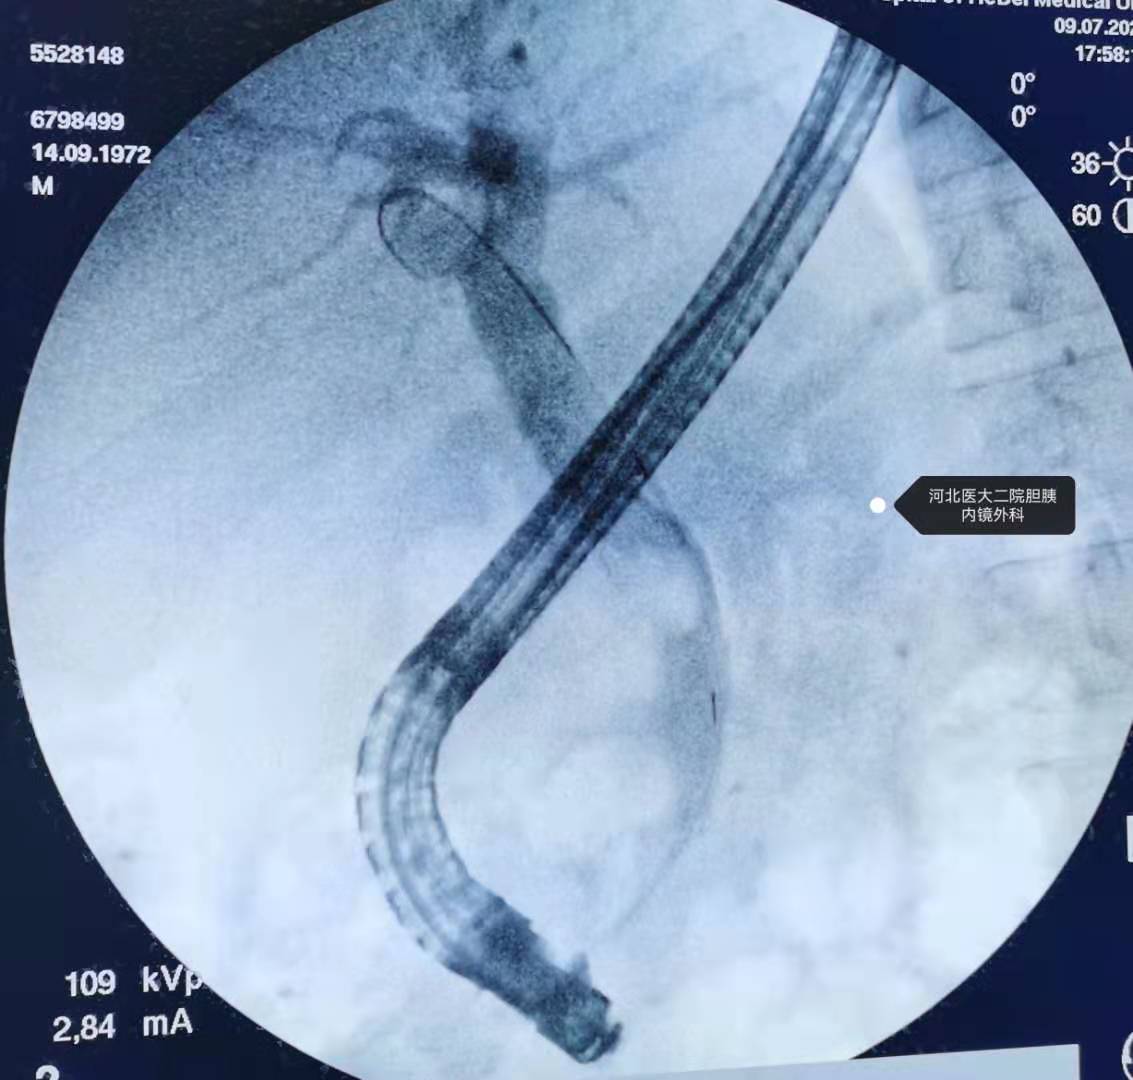

分享一例十二指肠乳头低位开口,憩室内乳头的ERCP取石操作

分享一个十二指肠乳头低位开口(十二指肠水平部),憩室内乳头的,还算顺利。

插管成功后,剩下的就简单了。

造影。

扩张。

取石。

球囊堵塞造影。

鼻胆管。